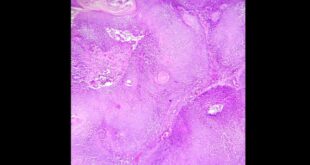

La piel a través del microscopio

Marisela Acosta Casanova

Médico anatomopatólogo

Adriana Mercedes Balza Haddad

Puedo confirmar que la dermatopatología, un tanto más que la dermatología –desde mi experiencia de 23 años de profesarla– otorga la inmediatez de resolver un problema, la satisfacción de poder ayudar a un otro, la comunidad de colaborar con otros especialistas y colegas, el entusiasmo que provoca una imagen y la felicidad absoluta de estar inmersa en el microscopio.